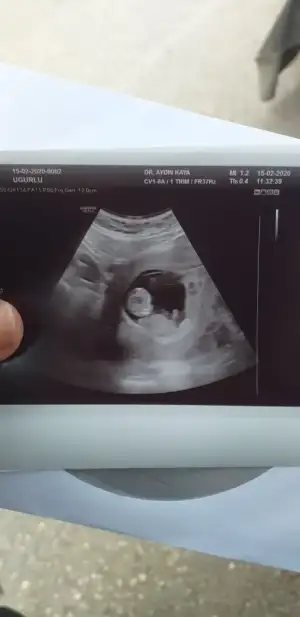

Netleşince anketimi oylarsanız sevinirimKesin olmamakla birlikte doktorumuzun ilk tahmini de kız![]()

Dün öğrendim sonucu sağlıklı bir kızçe annesi olucakmışım tahminlerin için teşekkürlerUsg kaç haftalık başka usg varsa paylaşın 11 +yada 12+

Ben de merak ediyorum ama biraz daha bekle denildi tahmininiz var mı acaba?